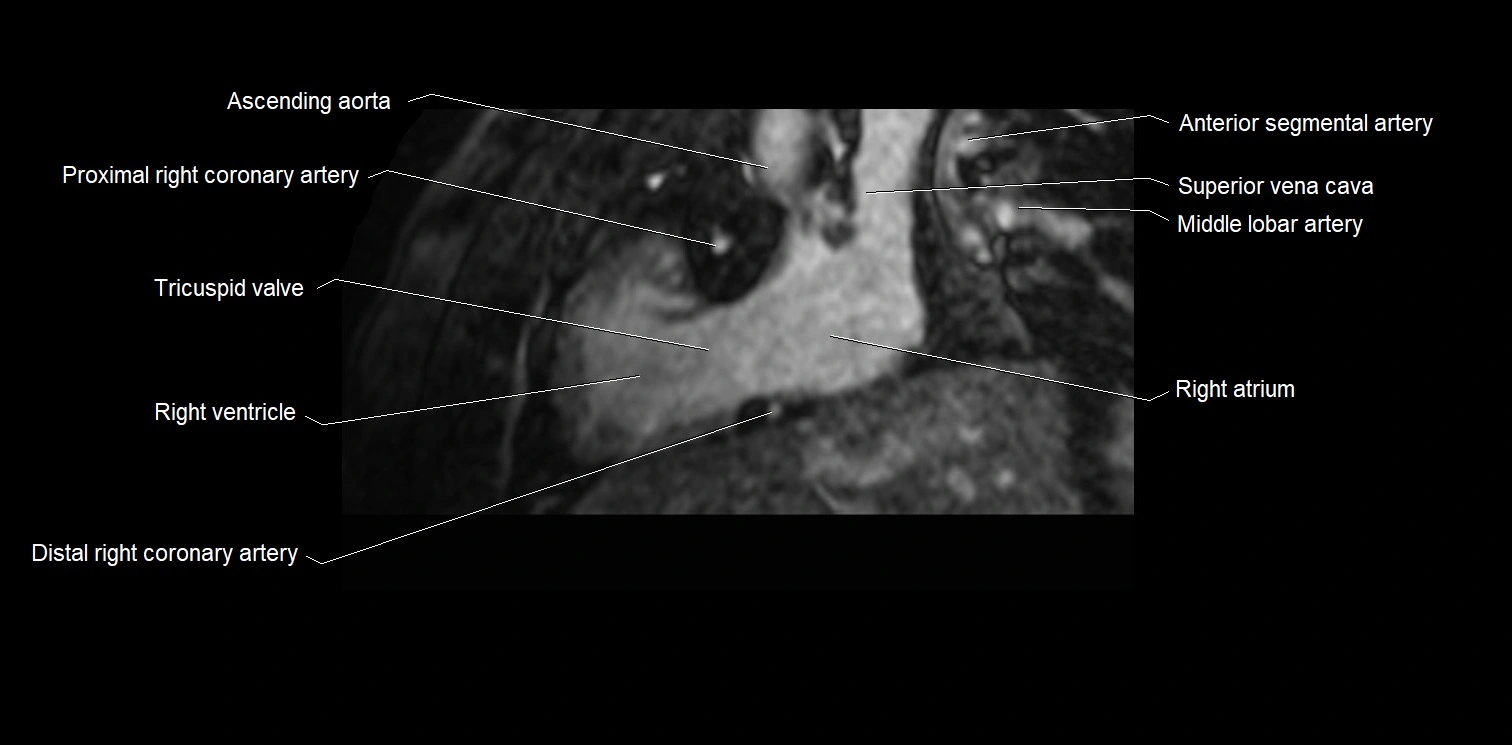

CT images